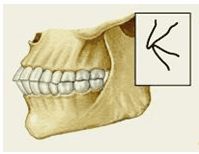

Кроме аномалий П. в сагиттальной плоскости существуют аномалии П. в вертикальной и трансверзальной плоскостях. К основным вертикальным аномалиям (определяются по отношению к горизонтальной плоскости) относится открытый и глубокий П. Открытый П. (рис. 7, а) — наличие щели между зубными рядами при их смыкании, чаще в области передних зубов, реже в области боковых. Иногда смыкаются только последние моляры, что приводит к выраженным нарушениям жевательной функции и особенно речи. При глубоком П. (рис. 7, б) передние зубы одной из челюстей в значительной степени перекрывают коронки зубов-антагонистов, нижние резцы не опираются на зубные бугорки верхних резцов, а соскальзывают к их десневому краю, что приводит к постоянному травмированию десен и неба; нижняя часть лица укорочена за счет уменьшения или дистального положения подбородка.

К трансверзальным аномалиям, определяемым по отношению к сагиттальной плоскости, относится перекрестный П. (рис. 7, в), при котором верхний зубной ряд в области боковых участков в значительной степени перекрывает нижний зубной ряд (латерогнатический П.) или нижний перекрывает верхний (латерогенический П.).

Кроме перечисленных выше видов патологического П. выделяют так называемый снижающийся прикус, который формируется вследствие стирания зубов или их утраты. При этом нижняя треть лица укорочена, расстояние между зубами увеличено (до 8—10 мм при норме 2—3 мм), углы рта опущены, носогубные складки резко выражены. При потере боковых зубов в детском или юношеском возрасте возможно дистальное смещение нижней челюсти. Снижающийся П., как правило, приводит к изменению соотношения элементов височно-нижнечелюстного сустава, в результате чего могут возникать боли в области сустава, затруднения и асимметрия движений нижней челюсти, щелканье или треск в суставе при его движениях, головные боли, шум в ушах.

Рис. 7а). Схематическое изображение челюстей при открытом прикусе.

Рис. 7б). Схематическое изображение челюстей при глубоком прикусе.

Рис. 7в). Схематическое изображение челюстей при перекрестном прикусе.